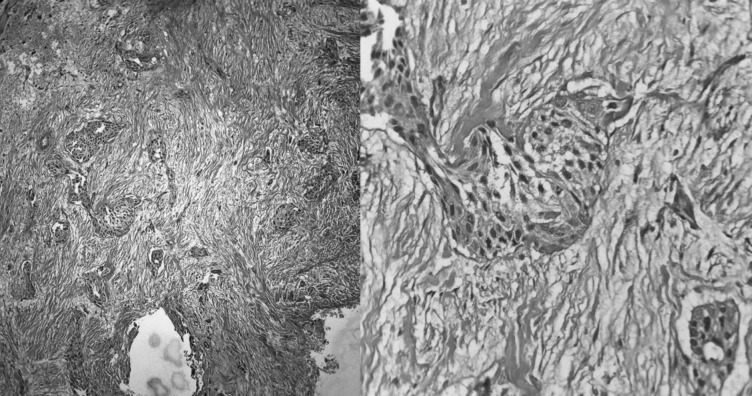

眼眶原发性鳞状细胞癌(SCC)非常罕见,仅占眼部肿瘤的一小部分,大多数病例继发于起源于附近结构的肿瘤或由于远处转移。我们报告一例60岁男性原发性眼眶鳞状细胞癌,讨论其诊断、影像学表现和多学科治疗。在认为不能手术后,患者接受了明确的放疗和同时进行的化疗。没有任何严重的治疗相关不良事件,患者在治疗后7个月获得完全的代谢反应,视力保持正常。从文献综述中可以看出,这类患者的治疗方法差异很大,放射治疗是一种成功的治疗方式,既能控制疾病,又能在可接受的毒性下保持视力。该病例强调了原发性眼眶SCCs治疗的复杂性,并强调了放疗在取得良好结果方面的有效性。

Primary squamous cell carcinoma (SCC) of the orbit is exceptionally rare, comprising only a small fraction of ocular tumours, with most cases being secondary to tumours originating from nearby structures or due to distant metastasis. We present a case of primary orbital SCC in a 60-year-old male, discussing its diagnostic workup, imaging findings, and multidisciplinary management. The patient underwent definitive radiotherapy with concurrent chemotherapy after being deemed inoperable. Without any severe treatment-related adverse event, the patient achieved a complete metabolic response at 7 months post-treatment with maintained vision. As evident from a review of the literature, treatment approaches vary widely in this group of patients, with radiotherapy emerging as a successful modality in achieving disease control while preserving vision with acceptable toxicity. This case underscores the complexity of managing primary orbital SCCs and highlights the efficacy of radiotherapy in achieving favourable outcomes.